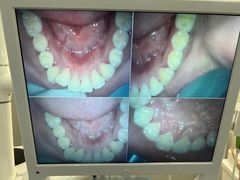

• 牙博士口腔品牌连锁(杨浦店)

• -牙博士口腔品牌连锁(杨浦店)